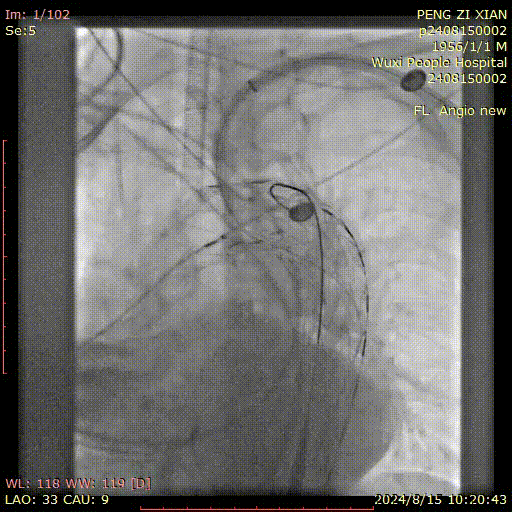

病史:54岁男性,发现胸腹主动脉夹层动脉瘤四天,2011年曾行A型夹层手术史,术后10年未复查。

手术方案:全麻下行胸腹主动脉夹层覆膜支架腔内隔绝,CA、SMA、双侧肾动脉体外开窗重建术。

I期腔内修复过程:

肾动脉至肠上区无破口,病情进展后又进行了二期干预

胸腹主动脉瘤四开窗内脏区重建+远端髂总大破口栓塞

术后效果良好,各分支通畅